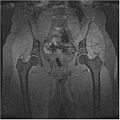

We have also proved that our algorithm works fairly well for hip dataset. Below are the MR images of Hip dataset we used.

The segmented output we got using our approach is